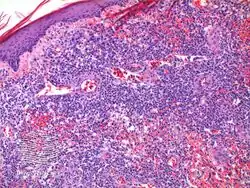

Lymphomatoid papulosis (LyP) is a rare skin disorder.[1] The overall prevalence rate of lymphomatoid papulosis is estimated at 1.2 to 1.9 cases per 1,000,000 population. [This is a widespread misinterpretation of a 1992 study saying "the period prevalence rate of lymphomatoid papulosis was estimated to be 1.9 per 1,000,000 population for Massachusetts and 1.2 per 1,000,000 population for Pennsylvania". The authors of that study said clearly "Our estimate of 1.2-1.9 cases per 1,000,000 population should be considered a minimum estimate of the prevalence rate". That estimate was based on the 78 patients involved in the study, not the LvP population. The study recruited 11 patients from Massachusetts and 15 from Pennsylvania [2]]. This rare condition has only been studied in depth since 1968.[3]

It can appear very similar to anaplastic large cell lymphoma.[4] Type "A" is CD30 positive, while type "B" is CD30 negative.[5]

It has been described as "clinically benign but histologically malignant."[6]

Diagnosis of lymphomatoid papulosis is done via the presentation and a skin biopsy[7]